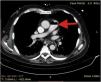

A 72-year-old man, previously independent, was admitted to the emergency department following cardiorespiratory arrest. A chest computed tomography scan (CTS) was requested. During the exam, the patient experienced sudden hypotension (65/20¿;mmHg) and poor peripheral perfusion. The exam was suspended and a fluid bolus was administered, resulting in transient reversal of the condition. Gas was detected in the injection system, which was replaced, and the exam was repeated. The CTS revealed gas embolism with an air-fluid level in the main pulmonary artery (marked with an arrow in Fig. 1), right atrium and right ventricle (marked with an arrow in Fig. 2), as well as in the left upper lobar artery (marked with an arrow in Fig. 3). Due to the venous gas embolism, he was transferred for treatment at a hyperbaric medicine center.